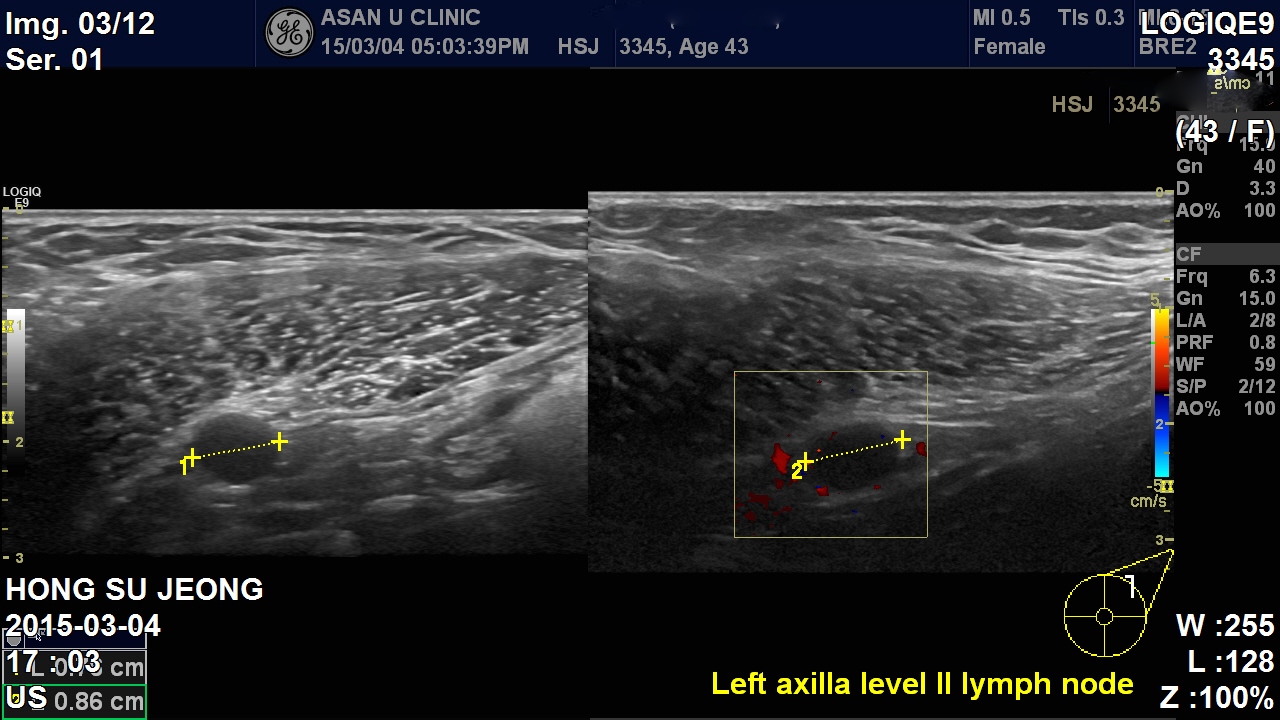

겨드랑이에도 림프절전이가 의심되었음.

유방의 몽우리 조직검사 및 겨드랑이 림프절 세포검사====> 침윤성 유관암의 좌측 액와전이